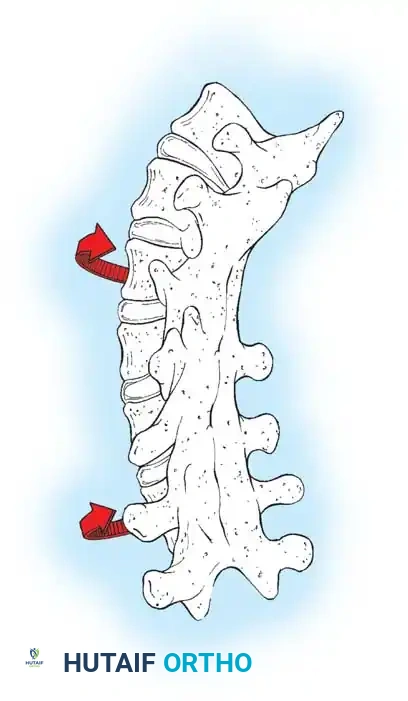

A profound complication unique to early-onset and juvenile scoliosis surgery is the "crankshaft phenomenon." In a landmark study of 24 children with infantile or juvenile idiopathic scoliosis, Hefti and McMaster demonstrated that achieving a solid posterior spinal fusion effectively arrests the longitudinal growth of the posterior elements. However, the neurocentral synchondrosis and the anterior vertebral body physes remain open and continue to grow anteriorly.

This continued anterior growth against a fixed posterior tether forces the vertebral bodies and intervertebral discs to bulge laterally toward the convexity of the curve. The spine essentially pivots on the solid posterior fusion mass, resulting in a severe loss of coronal correction, a dramatic increase in apical vertebral rotation, and the clinical recurrence of the rib hump deformity. Dubousset, Herring, and Shufflebarger have extensively documented and confirmed the biomechanics of this crankshaft phenomenon.